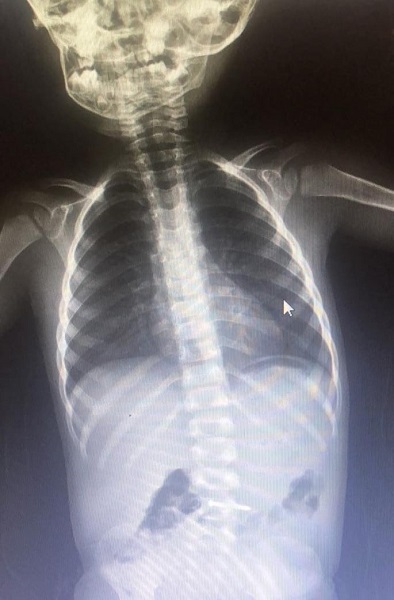

İnanılır gibi değil! Bakın 2 yaşındaki çocuk ne yuttu

Bursa'nın İnegöl ilçesinde çivi yutan 2 yaşındaki çocuk hastanelik oldu.

Olay, Mesudiye Mahallesi Sakin Sokak'ta meydana geldi. 2 yaşındaki Asil K., evde oynarken yerde bulduğu çiviyi ağzına atıp yuttu.

Olayı gören ailesi, küçük çocuğu hemen özel araçla İnegöl Devlet Hastanesi’ne götürdü. Yapılan tetkiklerde çivinin midesinde olduğu tespit edilen çocuk, ambulansla Bursa Yüksek İhtisas Eğitim ve Araştırma Hastanesi’ne sevk edildi.